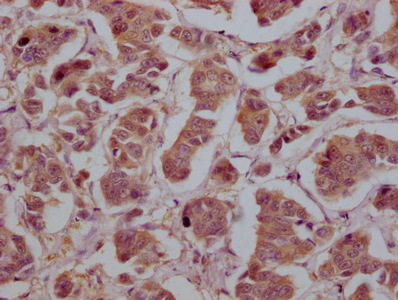

IHC image of CSB-MA026293A0m diluted at 1:200 and staining in paraffin-embedded human lung cancer tissue performed on a Leica BondTM system. After dewaxing and hydration, antigen retrieval was mediated by high pressure in a citrate buffer (pH 6.0). Section was blocked with 10% normal goat serum 30min at 37°C. Then primary antibody (1% BSA) was incubated at 4°C overnight. The primary is detected by a Goat anti-rabbit IgG labeled by HRP and visualized using 0.05% DAB.